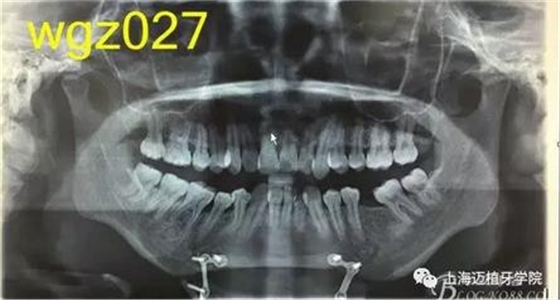

根據(jù)以下上傳的圖片及X線影像資料,你認為她的牙齒存在什么問題?應該如何進行矯治設計?

圖1

上海萬眾醫(yī)院正畸科進修醫(yī)生魏倩倩作業(yè)。 某女,25歲。 主訴:頦部術后自覺牙齒不齊,牙齒凸要求矯正。 既往史:曾有顳下頜關節(jié)疼痛史,于外院診斷為關節(jié)不可復性前移位伴髁突不對稱,行關節(jié)盤復位術。約3個月前在外院行頦成形術,現(xiàn)因牙齒不齊,牙齒凸前來就診。 口外檢查:正面觀,長面型,左右基本對稱,面下1/3過長,頦部明顯水腫,質硬; 側面觀,面型稍凸。 顳合關節(jié)檢查:無壓痛,左側彈響,兩側髁突運動基本一致。 口內(nèi)檢查:恒牙列,下頜前庭處縫合,傷口愈合良好??谇恍l(wèi)生情況一般,牙齦紅腫,LR2、LL6缺失,UR456舌傾與LR67成反合關系,UR3頰側突出移位,UR2UL2近中扭轉,UL1近中外翻唇傾,UR7UL7頰傾,LR6近中傾斜升高,LR5近中傾斜,LR4頰傾移位,LR3冠舌側傾斜,LL2近中扭轉冠頰傾,LL3舌傾,LL78近中傾斜。 模型分析:上頜前牙段擁擠度9.5mm,下頜前牙段擁擠度9mm,spee左右約3mm, LL5、LL7之間間隙約為5mm。上下中線右偏約1.5mm。全牙比約為80%,前牙比62%。磨牙關系:右側近中關系,UL6與LL7遠中尖對尖。尖牙關系:右側遠中關系,左側近中關系。 行為分析:患者已于外院行頦成形術,面型已改善,但患者仍覺得牙齒凸,說明患者非常重視面型問題,對美觀要求高。 頭顱側位片:面型稍凸,上唇在E線前約1.5mm,下唇在 E前約1mm 。 SNA: 85↑ SNB: 75↓ANB: 10↑ U1-L1: 113.6↓ U1-SN: 107.9 L1-M P: 88 ↓Y軸角:65.8 FH-MP: 37↑ SN -M P: 45↑ 曲面斷層片:28顆恒牙,LL6缺失,牙槽骨均位于釉牙骨質界以下,LR6、LL7近中牙槽骨角型吸收,頦部可見成型術鈦合板。左側升支較右側粗。 關節(jié)片:左右髁突不對稱,髁狀間隙右側明顯較左側寬,右側間隙清楚,大小勻稱 ,左側欠佳。 診斷:安氏3類 骨性2類 高角 上下前牙重度擁擠 中線不齊 間隙分析:下頜 , LL5與LL7之間的有5mm間隙,下頜擁擠度為9mm,整平下頜曲線需要約3mm間隙,下頜需要約12mm間隙,減去現(xiàn)有間隙還需要7mm間隙。上頜,擁擠度為9.5mm,擁擠主要集中在前牙段。 支抗分析:患者頦部術后仍覺面型凸(主要是上頜前突),所以除了要解決擁擠度外還需要內(nèi)收前牙,所以上頜需要強支抗?;颊逽NB為75,下頜發(fā)育不足,高角,相對低角病例來說,下頜磨牙較易前移。下頜前牙重度擁擠的情況下主張只解除擁擠不宜內(nèi)收(該患者系下頜后縮病例)。患者ANB為10°,本屬于正頜正畸聯(lián)合治療,現(xiàn)患者已做頦部成型術,患者面型得到改善,故患者現(xiàn)在主要為解決擁擠,少量內(nèi)收前牙,解決上前牙凸度。